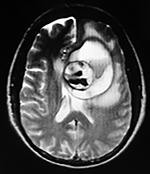

Paciente femenino de 29 años de edad con historial de cefalea crónica que presenta súbitamente disdiadococinesia y dismetría izquierda.

El estudio de RMN presenta una lesión bien circunscrita en hemisferio cerebeloso izquierdo con periferia de predominio hiperintenso en T1 y T2, y centro hipointenso, edema perilesional mínimo, así como una imagen de un vaso venoso alimentador que recorre hacia el ángulo pontocerebeloso izquierdo.

El estudio de control de RMN se observa la brecha quirúrgica y ausencia de lesión (figs. 1, 2 y 3).

Figura 1:

Lesión cerebelosa izquierda ponderaciones en T1 y T2, la flecha señala vaso nutricio hacia el ángulo pontocerebeloso izquierdo, se puede observar el centro de intensidad heterogénea con contenido quístico multiloculado y edema perilesional leve.